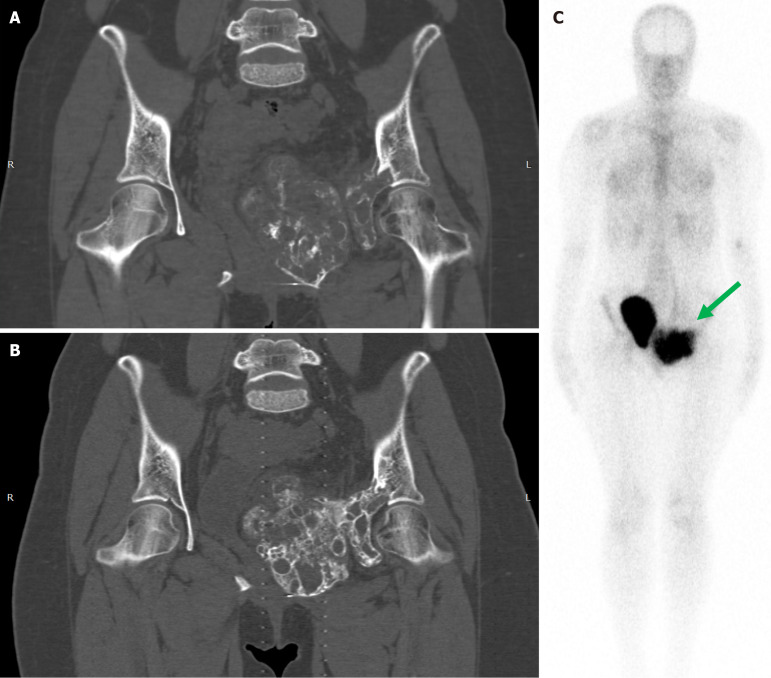

Results: As of December 2024, 43 patients have been reported in the literature who received DT for locally advanced/unresectable ABCs. There were 27 males and 16 females with a mean age of 15.8 years. At a median follow-up time of 15.5 months, there were 10 confirmed and two pathologically unconfirmed relapses after denosumab discontinuation. All 10 relapses occurred in patients in Group 1 at a median time of 13.5 months. Among patients in Group 2, with a median follow-up time of 12.5 months after completion of therapy, no local relapses were observed. The difference between local recurrence rates (32% vs 0%) is statistically significant (P value = 0.02). Kaplan-Meier estimates show the same trend with marginal statistical significance (P value = 0.085). Here we put forward a novel treatment algorithm.